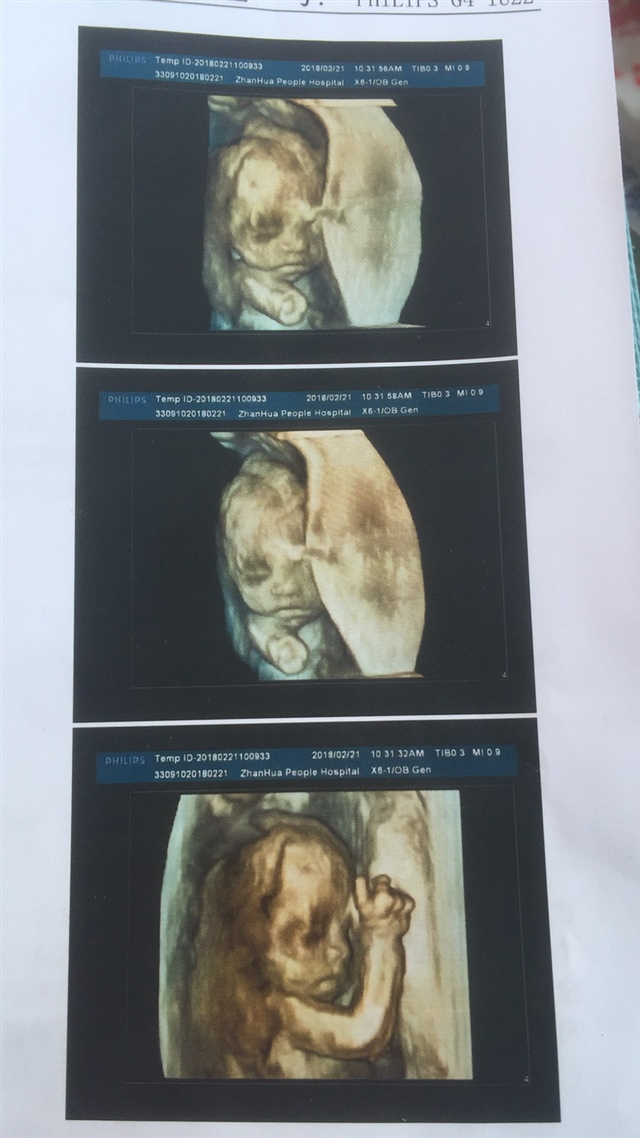

🎾娇🎾娇🎾娇🎾

孕13周+5天

太可爱了,太可爱了h

好清楚啊 为啥你们四维可以那么多的照片呢?

真清楚

女孩吗?听说女孩是抱着妈妈的

🎾娇🎾娇🎾娇🎾[帖主]:不知道,医生没告,第一个挺好奇的

为何你们的四维可以那么多张照片!

🎾娇🎾娇🎾娇🎾[帖主]:两张纸,在我们这做个四维500多